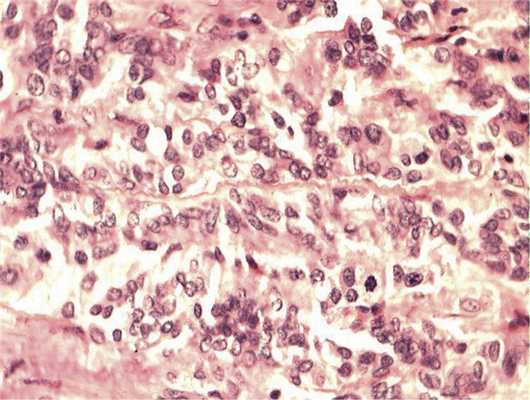

Отмечалось наличие ленточных структур из низкодифференцированных эпителиальных клеток (рис. 4). Параллельно встречались участки солидного строения из клеток с гиперхромными ядрами с признаками клеточного и ядерного полиморфизма. В них почти исчезает строма, появляются митозы, встречаются участки дистрофии и некроза (рис. 5). Опухоль врастает в ткань ДЗН с переходом за laminacribrosa, но не достигает линии отсечения (рис. 6). В таком виде опухоль обладает местнодеструирующим характером роста и может давать метастазы, глубоко инфильтрируя прилежащую к ДЗН ткань хориоидеи. Окончательный гистологический диагноз: злокачественная медуллоэпителиома центрального отдела сетчатки с вовлечением ДЗН и инвазией перипапиллярной хориоидеи, с глубоким прорастанием по зрительному нерву, не достигая линии отсечения.

Рис. 5. Зоны солидного роста опухоли. Клеточный полиморфизм с фигурами митозов. Окраска гематоксилином и эозином. Ув. 400.